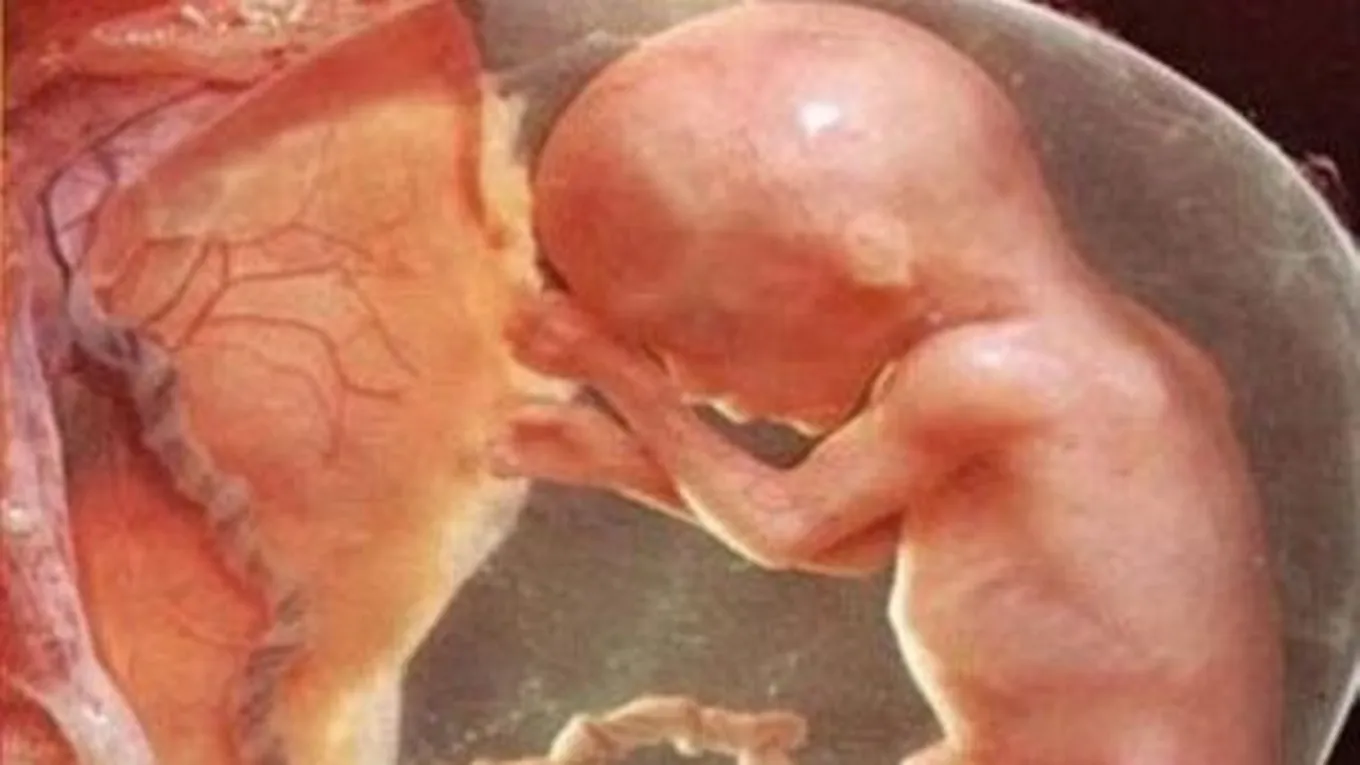

- أمّا بالنسبة لطول ووزن الجنين، فيصل طوله إلى 25سم، ووزنه حوالي نصف كيلو غرام أو ما يعادل 450 غراماً.

- ينمو الجنين خلال هذا الشهر بشكل سريع جداً.

- تبدأ الأعضاء الداخلية بالنضج تدريجياً.

- إضافةً إلى أنّ الجنين خلال هذه الفترة من الحمل، يبدأ بتنظيم نومه ويمكن للأم أن تشعر به حين يستيقظ؛ كما يستطيع في هذا الشهر أيضاً أن يتقلب بين اليمين واليسار.

- يمكن رؤية الجنين بشكل واضح من خلال الأمواج فوق الصوتية للتأكد من جنسهِ، ذكر أم أنثى.